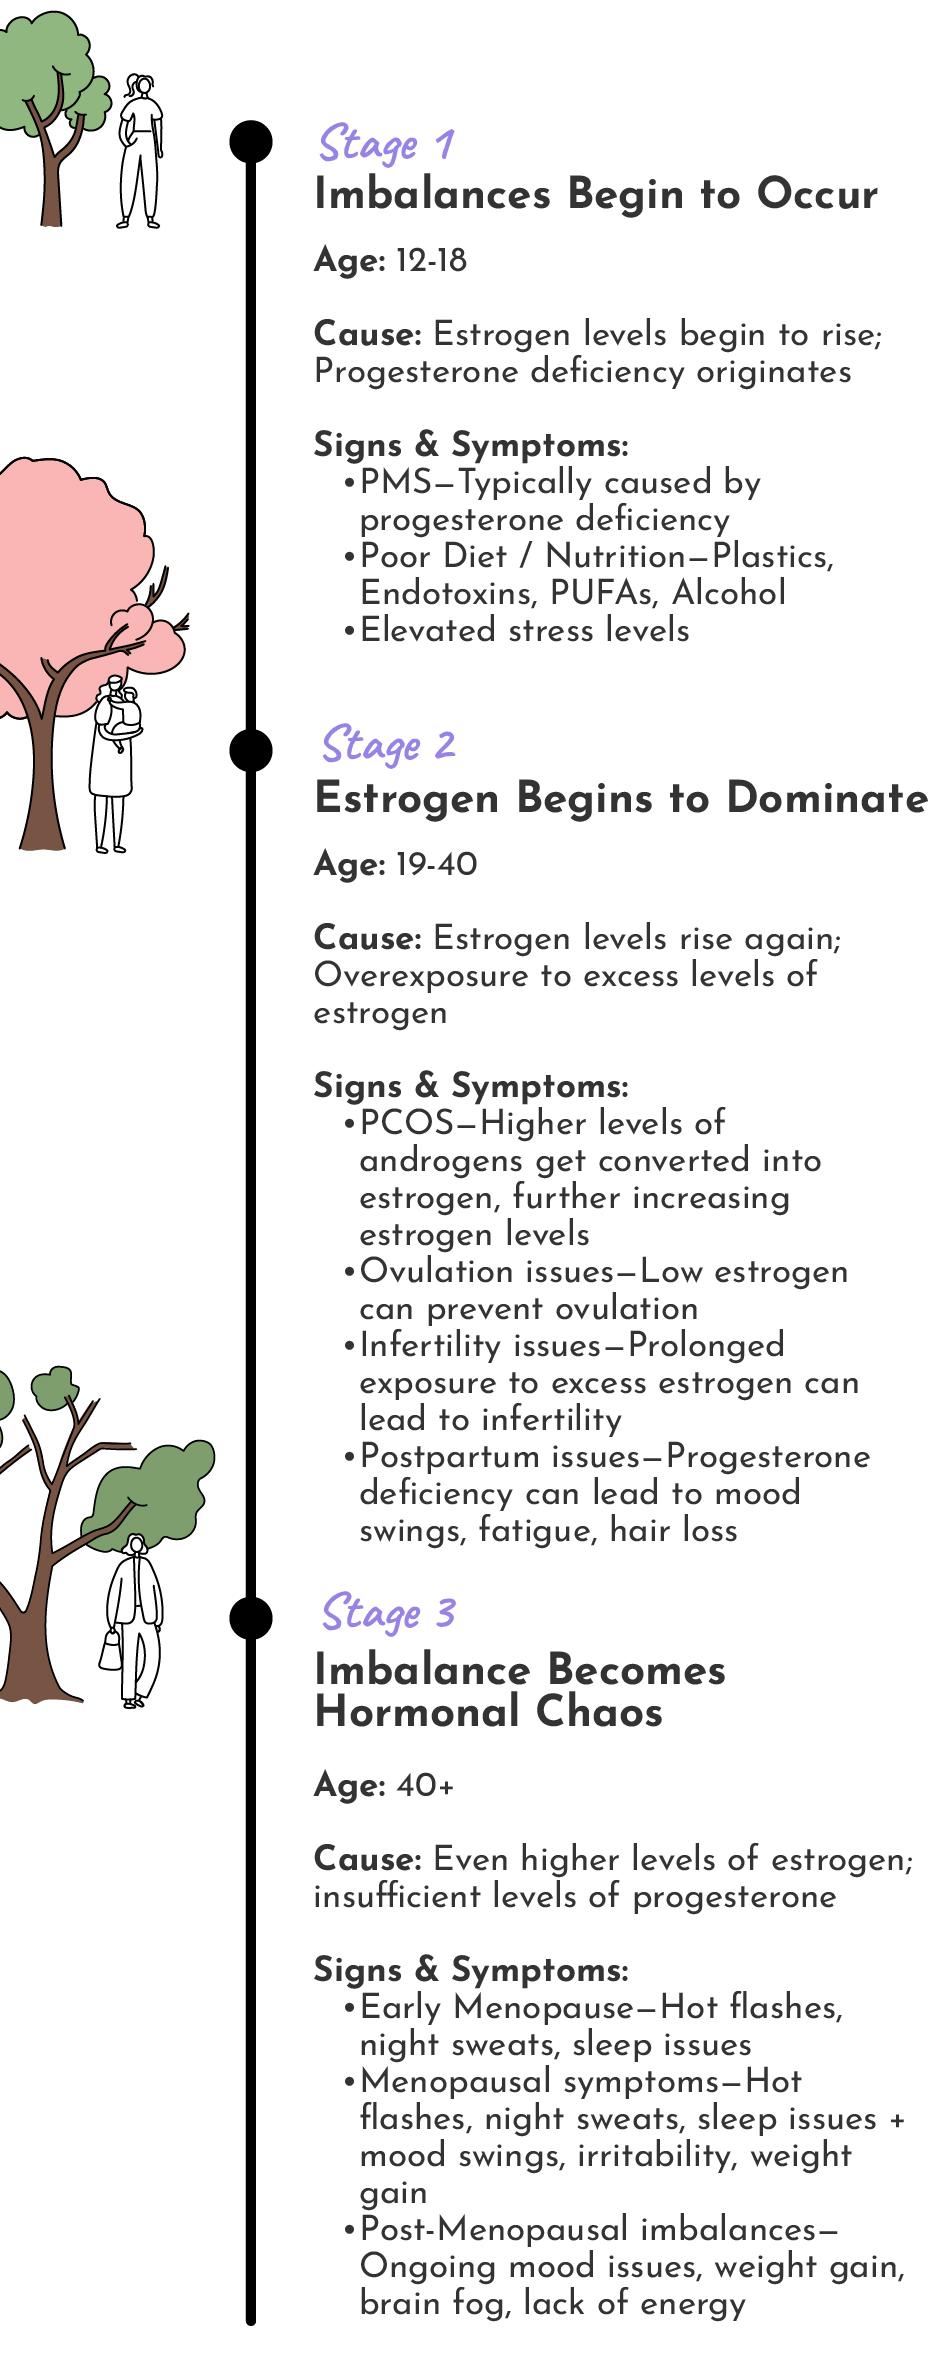

Estrogen Dominance can happen at any one of the following stages or be present during all three.

Age: 12-18

Cause: Estrogen levels begin to rise; Progesterone deficiency originates

Signs & Symptoms:

PMS—Typically caused by progesterone deficiency

Poor Diet / Nutrition—Plastics, Endotoxins, PUFAs, Alcohol

Elevated stress levels

Age: 19-40

Cause: Estrogen levels rise again; Overexposure to excess levels of estrogen

Signs & Symptoms:

PCOS—Higher levels of androgens get converted into estrogen, further increasing estrogen levels

Ovulation issues—Low estrogen can prevent ovulation

Infertility issues—Prolonged exposure to excess estrogen can lead to infertility

Postpartum issues—Progesterone deficiency can lead to mood swings, fatigue, hair loss

Age: 41+

Cause: Even higher levels of estrogen; insufficient levels of progesterone

Signs & Symptoms:

Early Menopause—Hot flashes, night sweats, sleep issues

Menopausal symptoms—Hot flashes, night sweats, sleep issues + mood swings, irritability, weight gain

Post-Menopausal imbalances—Ongoing mood issues, weight gain, brain fog, lack of energy

Estrogen Dominance can happen at any one of the following stages or be present during all three.